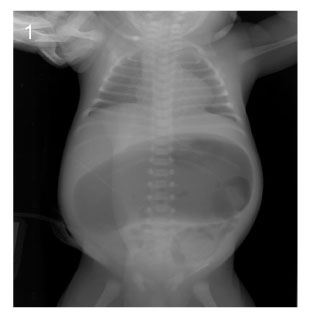

Fig. 1

Image of simple X-ray at the age of 8days (Case No. 3).

Fig. 1 Image of simple X-ray at the age of 8days (Case No. 3).